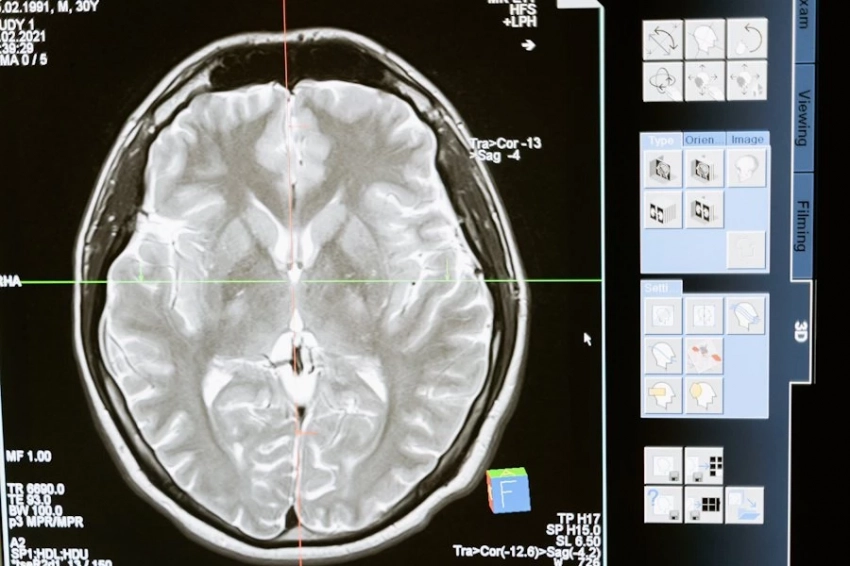

Старческая деменция — это заболевание, при котором у человека постепенно нарушаются память, способность к логическому мышлению и концентрации внимания. В итоге когнитивные функции существенно снижаются, а личность претерпевает значительные изменения.

В журнале Journal of Aging Research and Lifestyle опубликовано исследование, где отмечается, что тяжелая форма пародонтита, известная как заболевание десен, может быть связана с ухудшением работы мозга. Ученые выявили сильную корреляцию между пародонтитом и легкими когнитивными нарушениями, указав на необходимость дополнительной оценки пациентов с этим заболеванием.

Специалисты считают, что такая связь может объясняться несколькими механизмами. Например, бактерии из полости рта способны проникать в кровоток, достигая мозга и производя токсины, которые повреждают нервные клетки.

Исследование, представленное в журнале Oral Diseases, дополнительно подтверждает двунаправленный характер этой взаимосвязи. Снижение когнитивных способностей у людей с деменцией часто сопровождается ухудшением здоровья полости рта, так как пациенты теряют способность заботиться о себе. Кроме того, деменция рассматривается как один из ключевых факторов, способствующих развитию тяжелого пародонтита.

Японские ученые подчеркивают важность регулярных визитов к стоматологу и ранней диагностики когнитивных изменений. Они отмечают, что деменция обычно развивается в течение 10 лет, но на ранних стадиях болезнь поддается лечению, что позволяет замедлить ее прогрессирование.